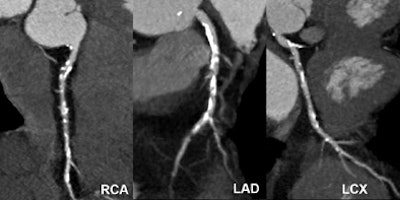

![]() |

| Nonsignificant mixed stenosis of the mid-LAD, false-positive diagnosis with dual-source CT coronary angiography (rated as 60% to 70% stenosis). |